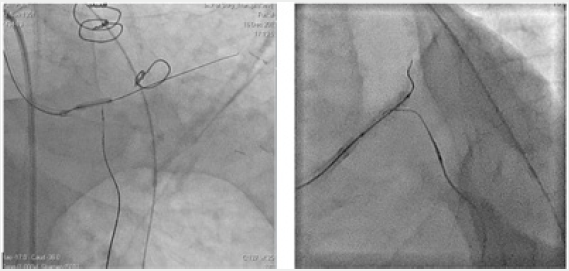

Figure 5: Retrograde reclamation of OSLKA in a patient after CABG. Method Reverse Cart. The balloon-catheter is positioned antegradeally. Retrograde, a microcatheter Corsair and a conductor “Gaia 3” were carried through the shunt to the OB of the LCA.